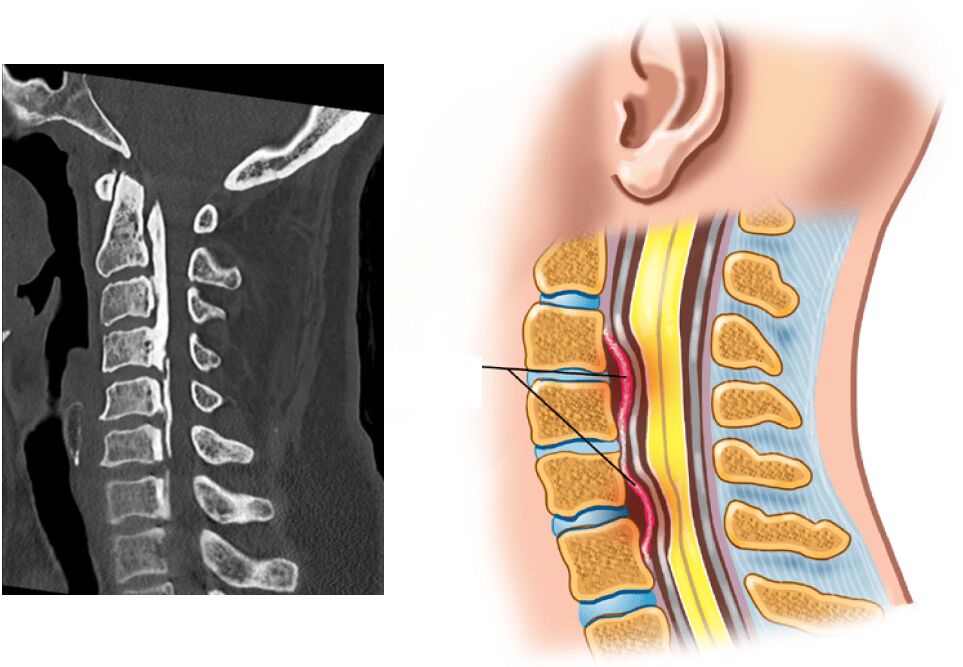

解剖題與疾病題,先看central stenosis:

central stenosis=直接壓迫到脊髓腔(Spinal Canal) 導致的脊髓狹窄

可能(C) 後縱韌帶鈣化(ossification of the posterior longitudinal ligament)

後縱韌帶在椎體後側/脊髓腔前側,鈣化很慘,手術難度高

最不可能(B) 頸部前彎動作,使髓腔的前後徑變小

我找不到FLEX/EXT對頸椎Spinal Canal空間的影響,但從magee可知,頸椎FLEX會疼痛降低,EXT疼痛增加,所以頸椎EXT才會使Spinal Canal變小